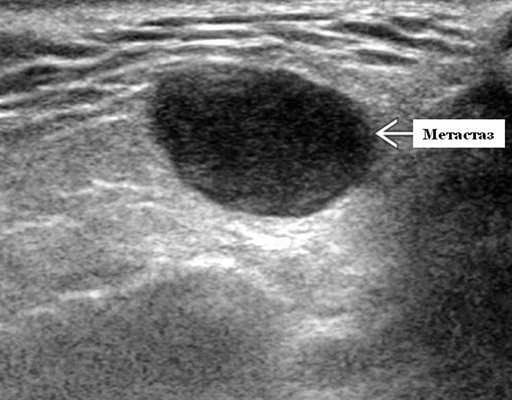

- Одиночные или множественные гипоэхогенные образования при известном распределении внутрипаротидных лимфоузлов.

- На ультразвуковом сканировании образование четко или плохо определено (экстранодальное распространение)

- На УЗИ определяется аномальная внутренняя архитектура ± эхогенные ворота, эхогенность однородная или неоднородная с внутренними кистозными участками в некротических узлах

- ± Метастатические шейные лимфатические узлы

Серошкальное УЗИ. Одиночные или множественные гипоэхогенные образования в известном распределении внутрипаротидных лимфоузлов. Хорошо выраженный или слабо окаймленный (экстранодальное распространение). Экстранодальное распространение. Обратите внимание на местную инвазию интрапаротидной наружной сонной артерии (ВСА), ретромандибулярной вены или экстрапаротидных мягких тканей. Аномальная внутренняя архитектура ± эхогенные ворота. Однородный или неоднородный вид с внутренними кистозными участками в некротических узлах ± метастазы в шейные лимфатические узлы